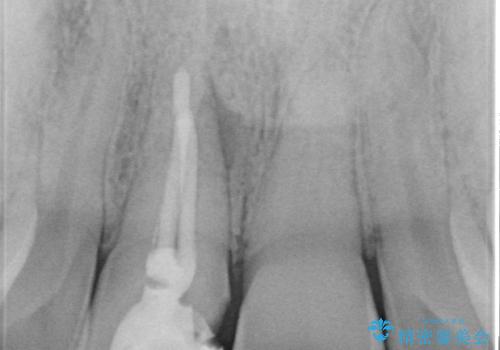

- 右上1番目の前歯の変色が気になるといらっしゃった方の症例です。

再根管治療後、オールセラミッククラウンによる補綴を行いました。